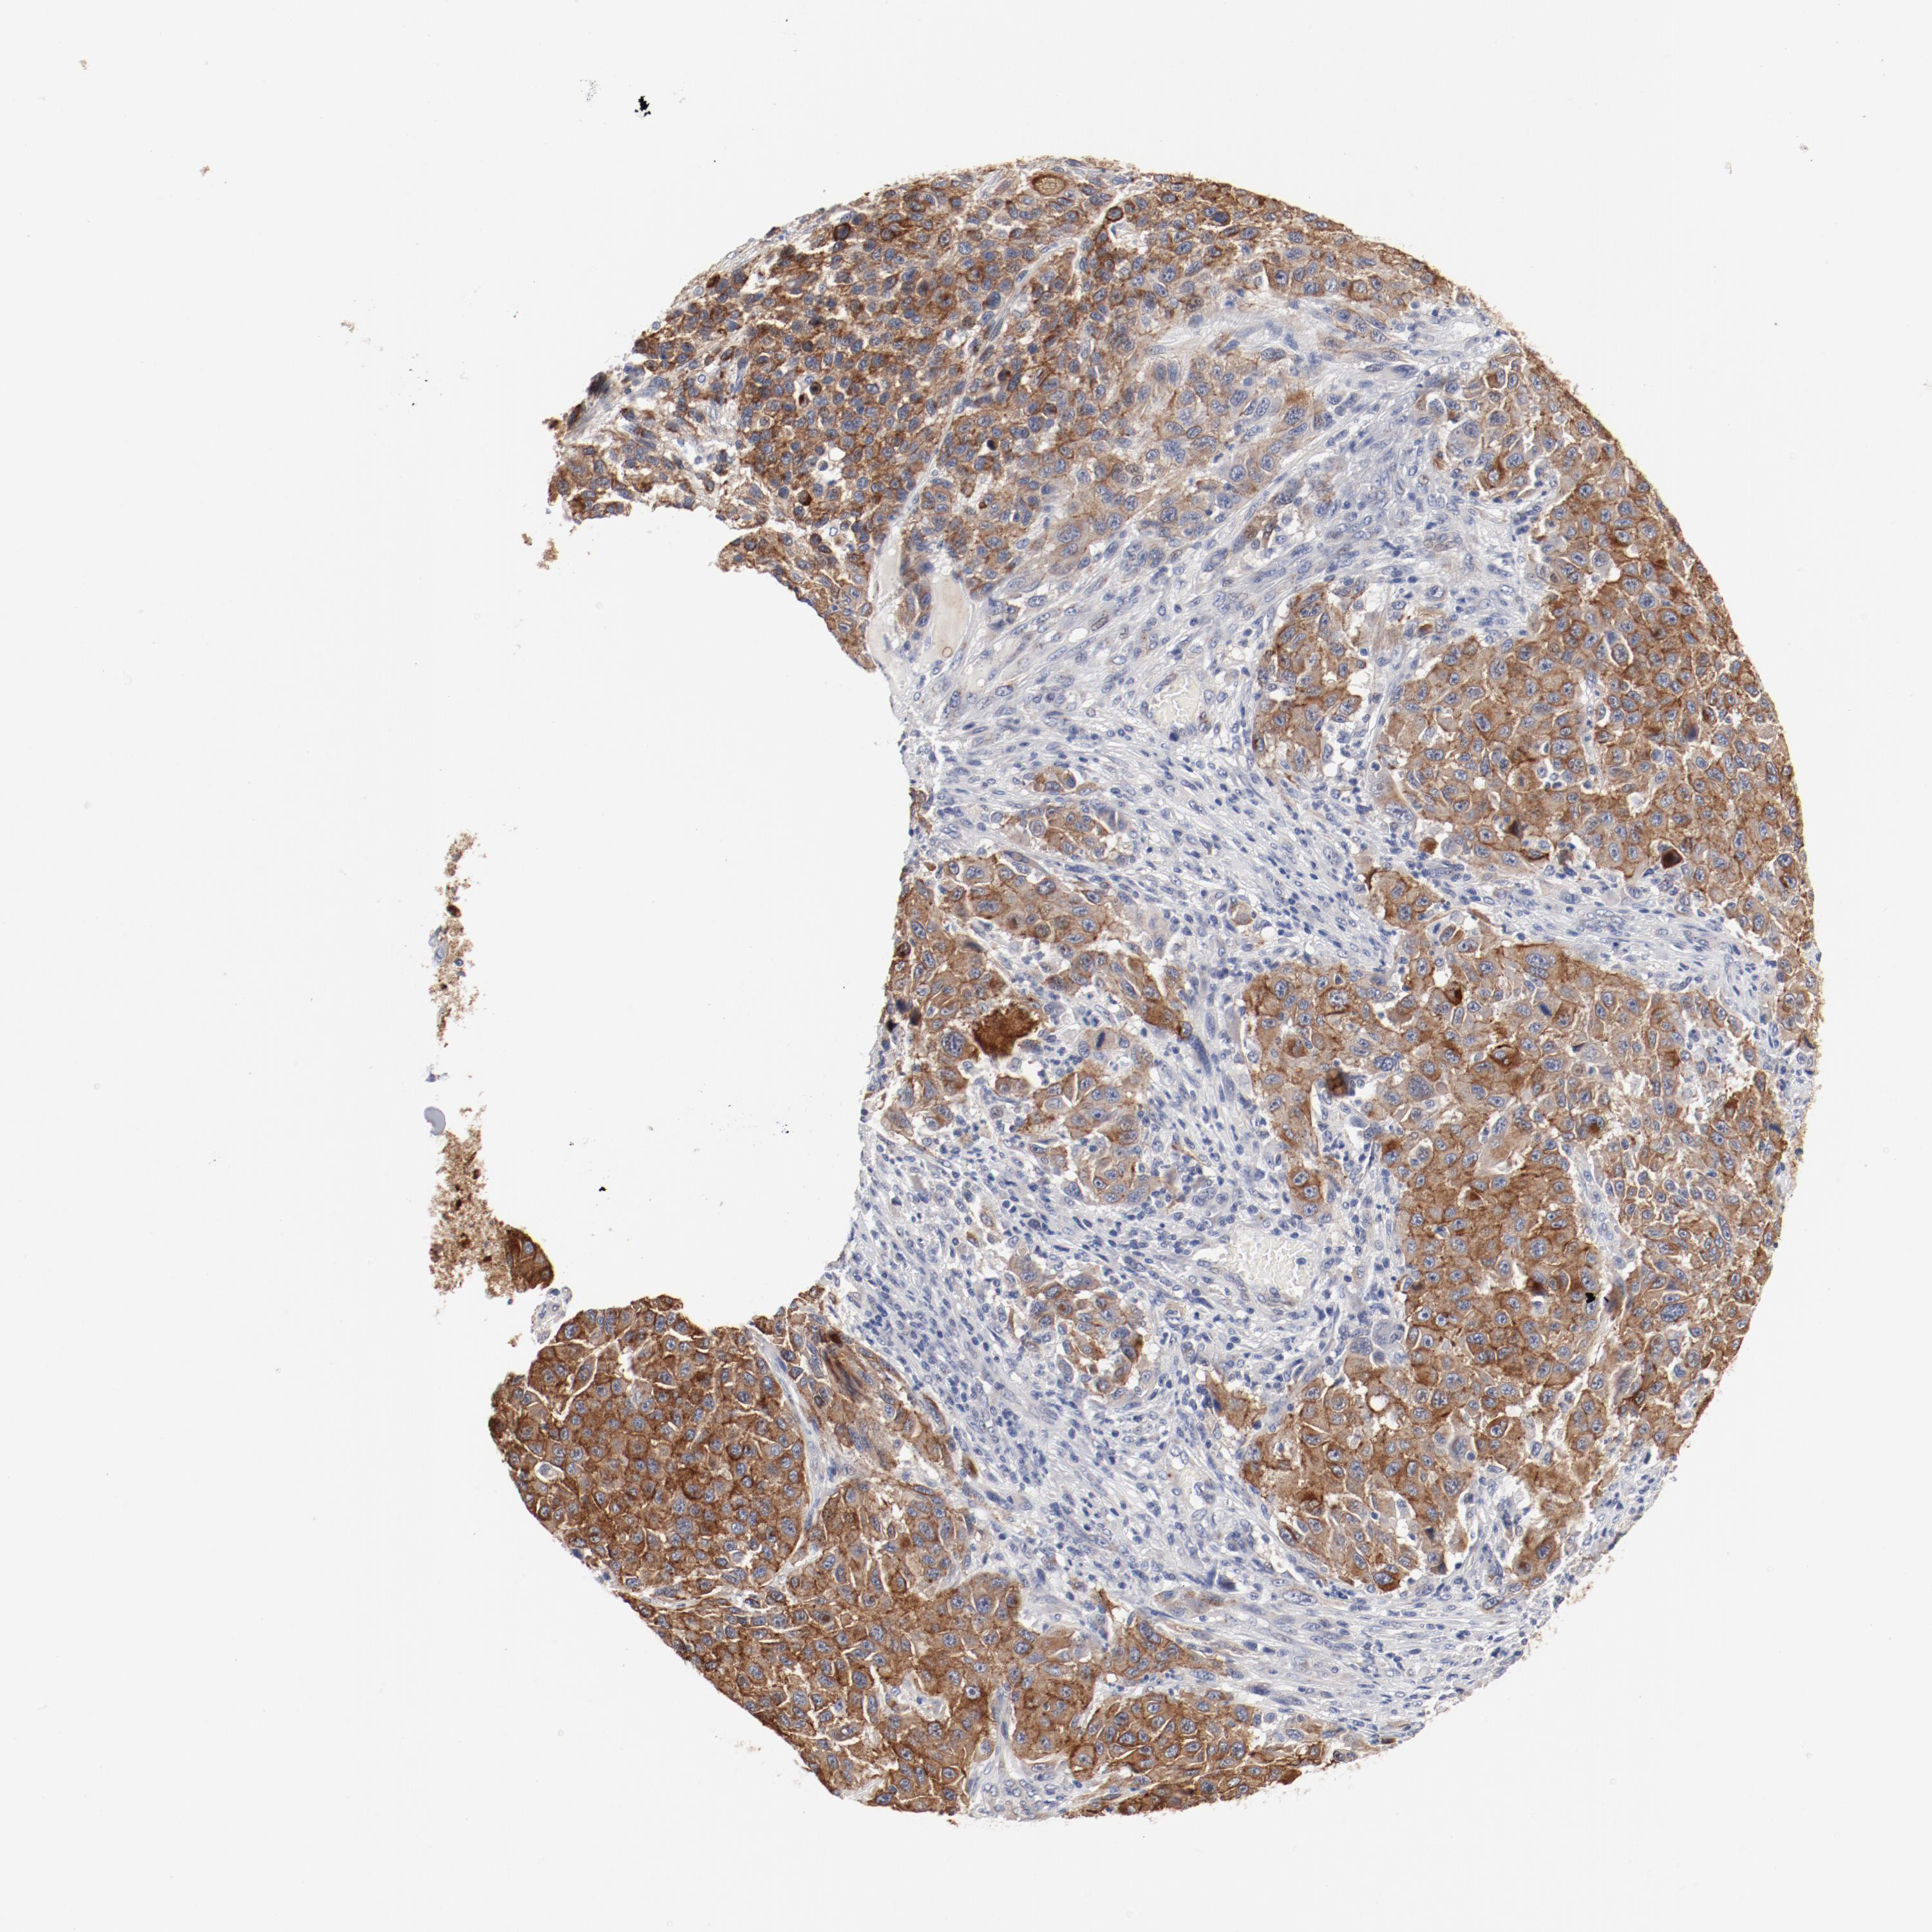

MELANOMA - Protein expressioni

A mouse-over function shows sample information and annotation data. Click on an image to view it in a full screen mode. Samples can be filtered based on level of antibody staining by selecting one or several of the following categories: high, medium, low and not detected. The assay and annotation is described here.

Note that samples used for immunohistochemistry by the Human Protein Atlas do not correspond to samples in the TCGA dataset.

Antibody stainingi

Antibody staining in the annotated cell types in the current human tissue is reported as not detected, low, medium, or high, based on conventional immunohistochemistry profiling in selected tissues. This score is based on the combination of the staining intensity and fraction of stained cells.

Each image is clickable and will lead to virtual microscopy that enables deeper exploration of all samples and also displays staining intensity scores, fraction scores and subcellular localization as well as patient and tissue information for each sample.

Antibody HPA003648

Staining

High

Medium

Low

Not detected

Intensity

Strong

Moderate

Weak

Negative

Quantity

>75%

75%-25%

<25%

None

Location

Nuclear

Cytoplasmic/membranous

Cytoplasmic/membranous,nuclear

Malignant melanoma, Metastatic site